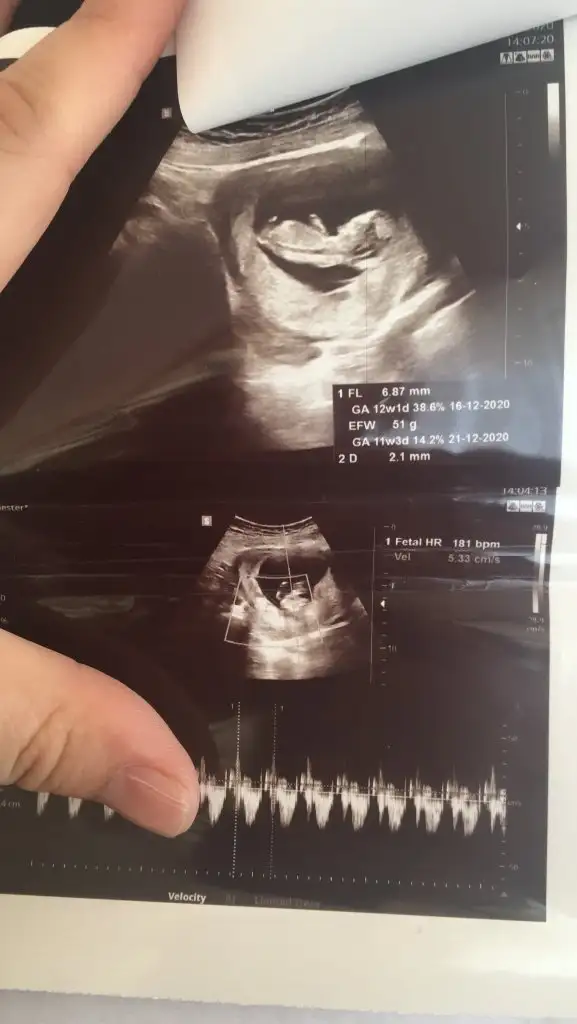

Cuma günü kontrol var bakalim ozaman atarim yine daha net belli olur

TamamCuma günü kontrol var bakalim ozaman atarim yine daha net belli olur